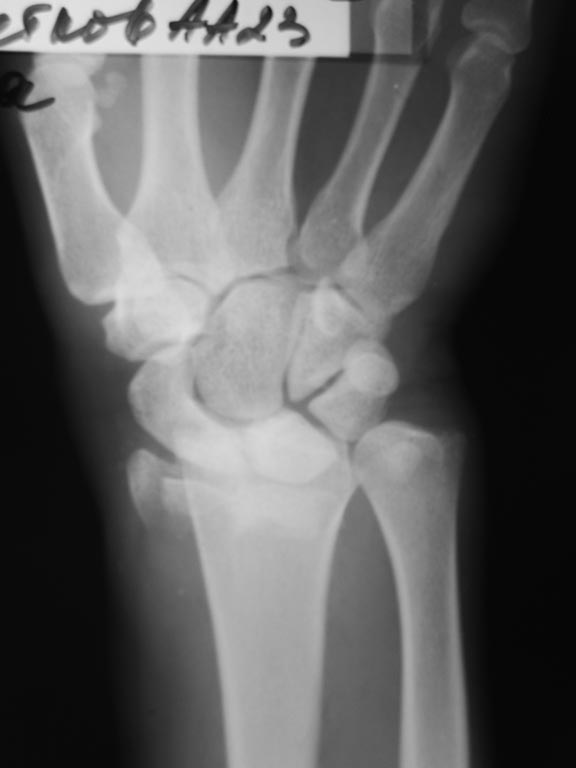

Рентгенограммы:

Это классический переломо-вывих в лучезапястном суставе, выделенный АО в отдельную подгруппы - 23-В2.3. В свежем случае здесь показано закрытое вправление и наружная фиксация повязками или аппаратом, в качестве окончательного метода для предотвращения нестабильности сустава рекомендуется восстановление капсулы сустава, в первую очередь тыльной - т.е. репозиция и фиксация всех этих мелких фрагментов, послеоперационная иммобилизация аппаратом внешней фиксации